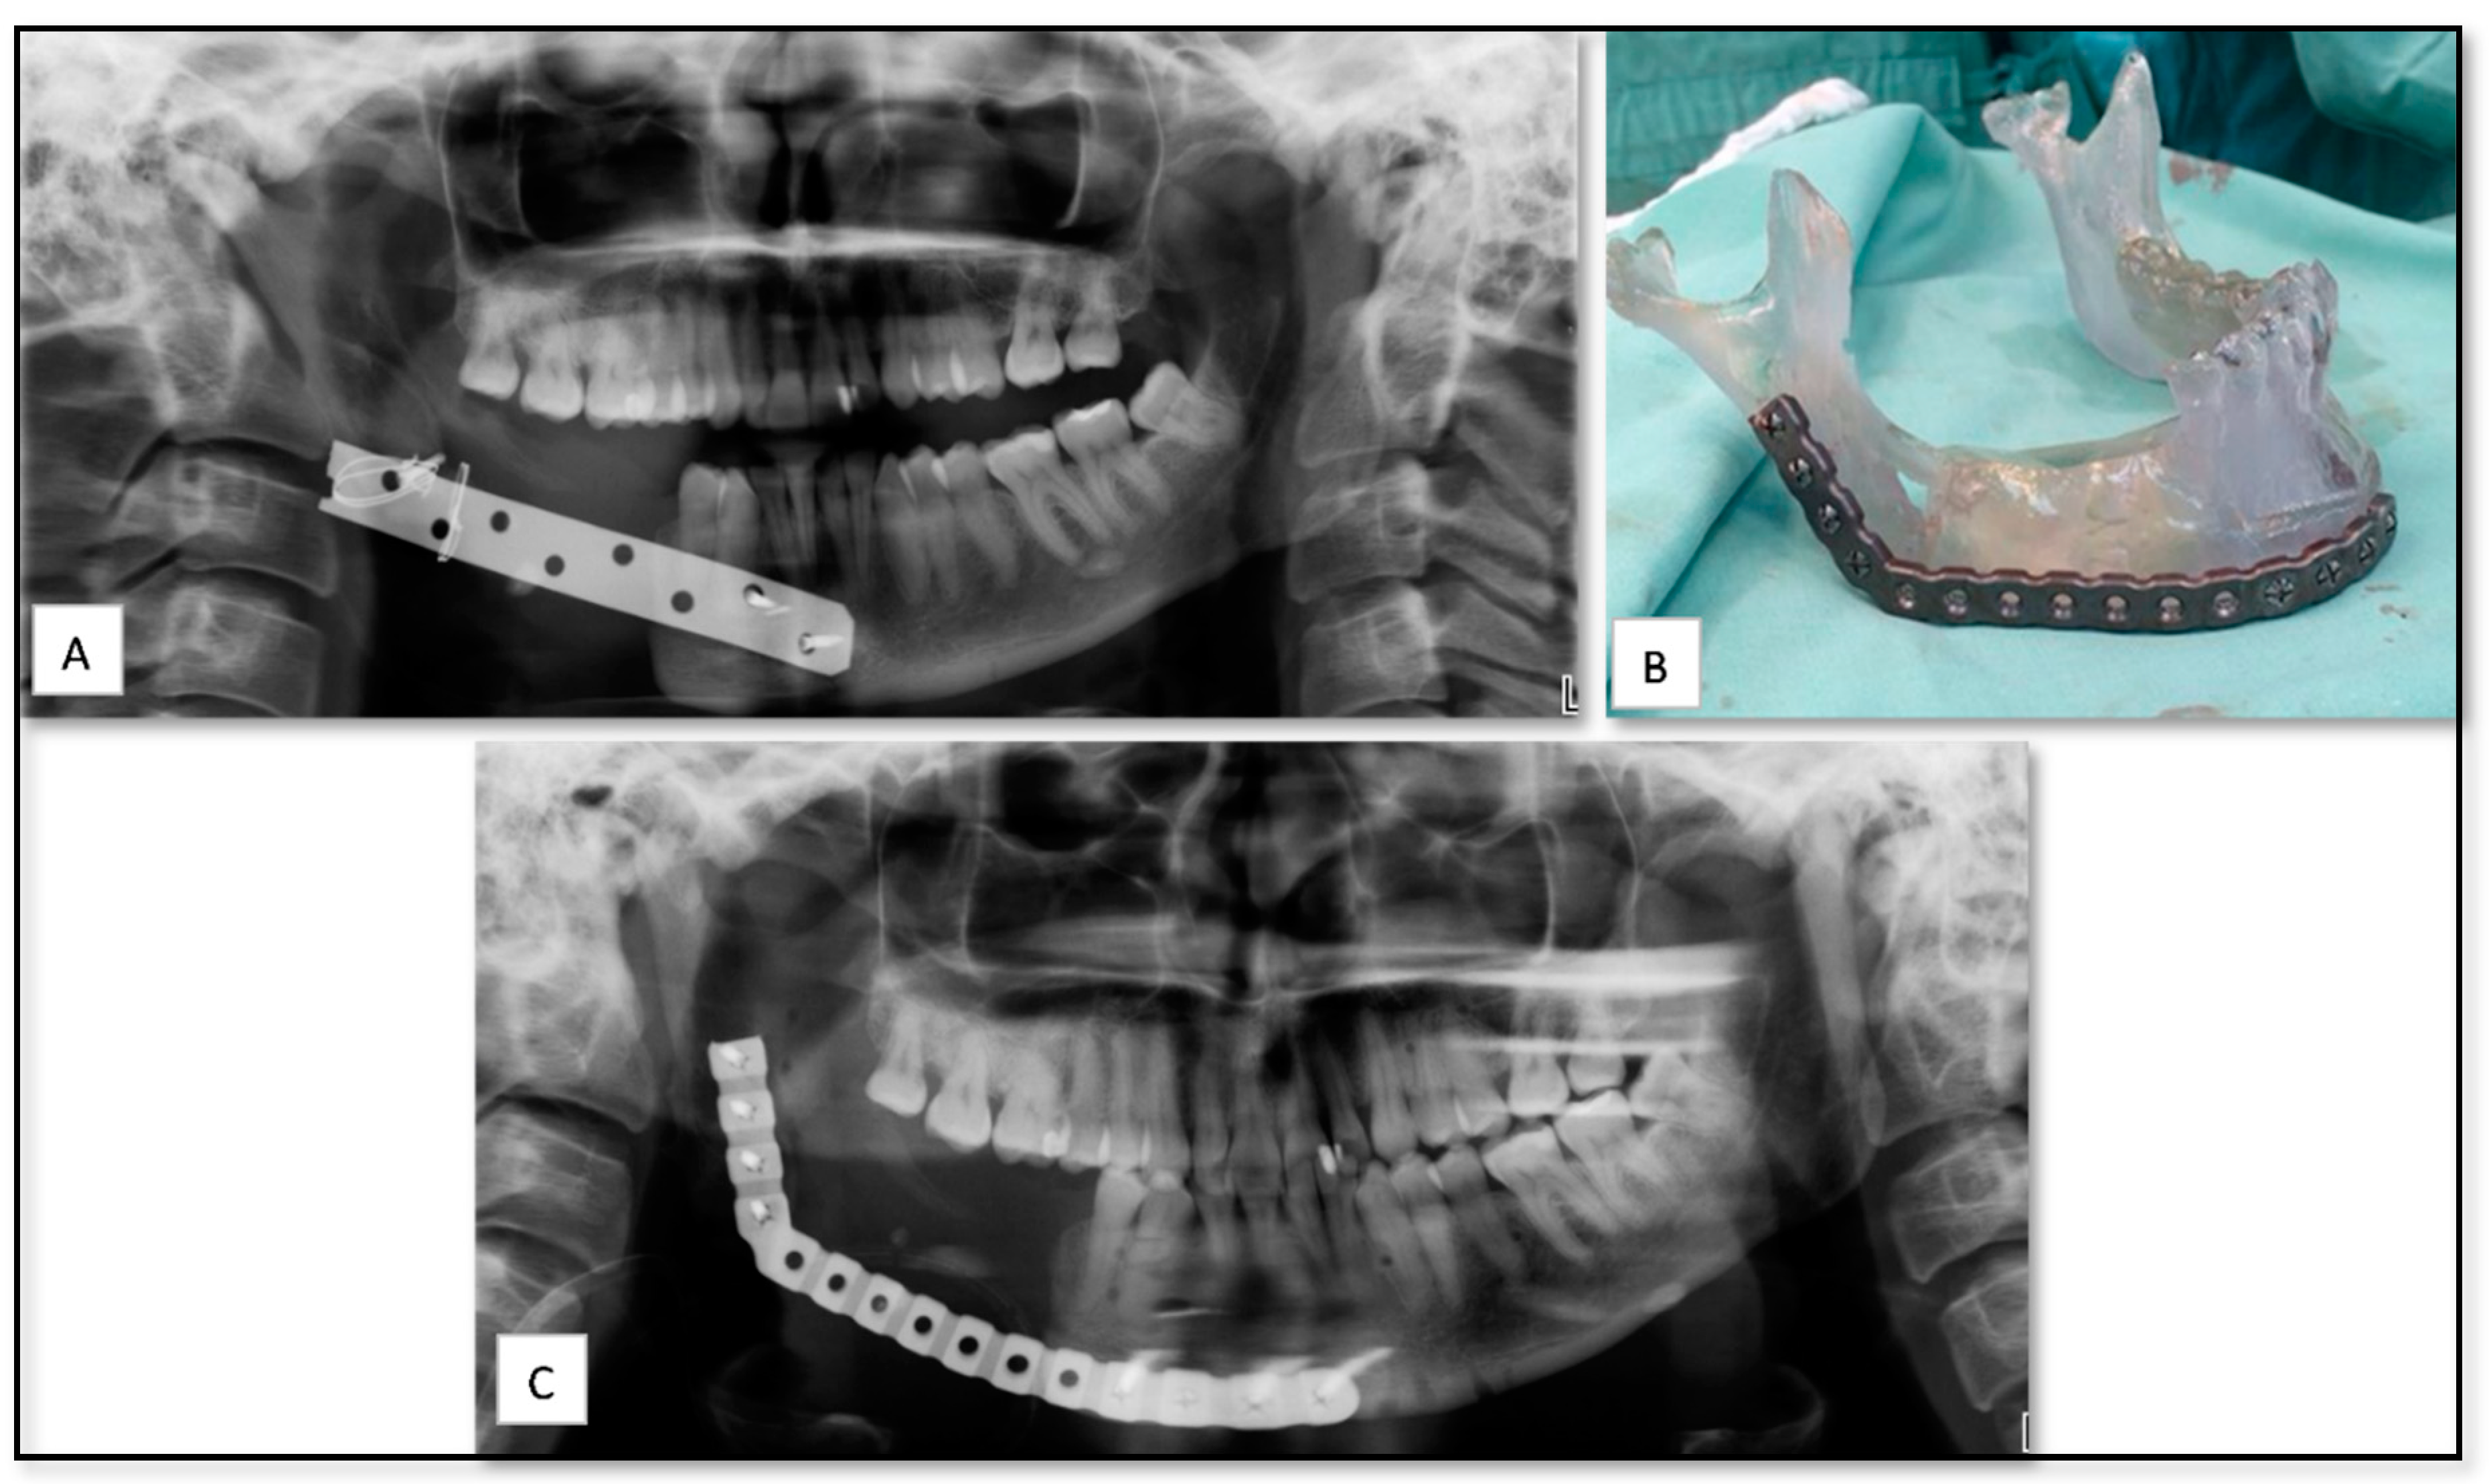

5.4. AM for Temporomandibular Joint (TMJ) Reconstruction Surgery Due to Oncologic Rresection

5.5. AM for Producing PSI for Reconstruction of Large Mandibular Defect after Tumor Resection

| 1 | 33 | F | Trauma | Mandible | SLA model for pre-bending of reconstruction plate | Resin | − | Mild edema |

| 4 | 64 | M | Oncology | Mandible | PSI of mandibular body with ramus and condyle | Titanium | − | Moderate edema |